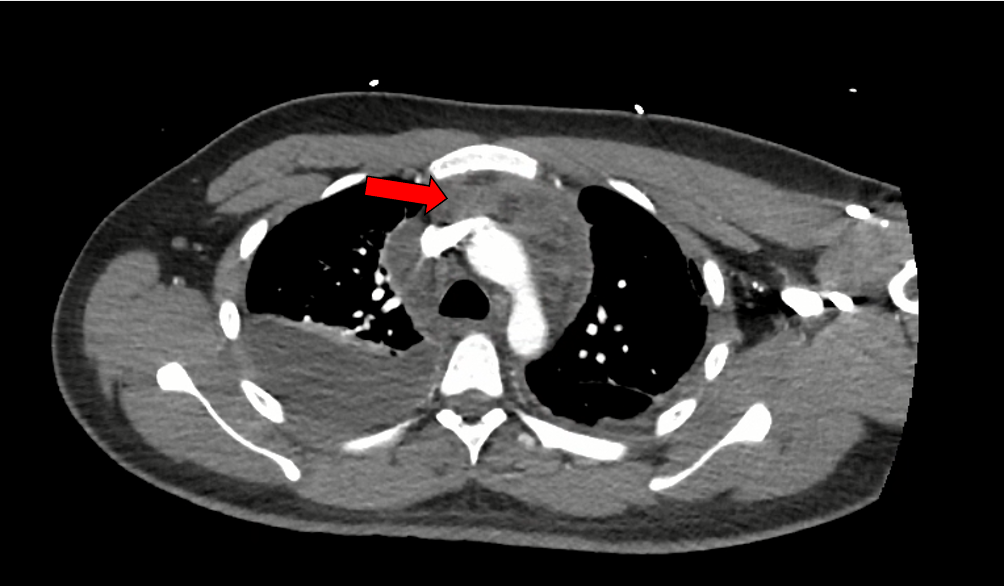

Case Presentation: A 23-year-old male with no significant past medical history presented to an urgent care with six days of fevers, chills, and cough. He was diagnosed with influenza B and discharged home with supportive care. His symptoms continued to progress, and he developed pleuritic chest pain. He presented to the emergency department on day 8 of his illness with a heart rate of 144. A computed tomography (CT) of the pulmonary arteries was negative for pulmonary embolism but showed evidence of pneumonia, bilateral pleural effusions, and a small pericardial effusion. Lab work revealed a mild leukocytosis of 11.79 K/mcL, C-reactive protein 364.3 mg/L, estimated sedimentation rate 42 mm/h, and lactic acid 3.4 mmol/L. Complete metabolic panel, troponin, anti-nuclear antibody, urinalysis, Streptococcus pneumoniae urine antigen, Legionella spp. urine antigen, thyroid stimulating hormone, HIV, group A Streptococcus throat culture, and sputum cultures were unremarkable. He was initially started on vancomycin, ceftriaxone, and three days of azithromycin for treatment of pneumonia, colchicine for pericarditis, and five days of oseltamivir for influenza infection. MRSA probe was negative, so vancomycin was discontinued. Blood cultures returned with one of two positive for methicillin-susceptible Staphylococcus aureus (MSSA). He underwent bilateral thoracenteses with fluid analysis revealing exudative effusions. On day seven of his hospital stay, the ceftriaxone was transitioned to cefazolin 2 g IV every 8 hours. A repeat CT chest was ordered due to the patient’s continued chest pain and it showed a confluent, homogenous mass in the anterior mediastinum consistent with an abscess. Percutaneous biopsy of the mediastinal mass grew MSSA on culture. On day 10, a repeat CT showed partial improvement in the mediastinal abscess size, so the decision was made not to proceed with surgical washout. He was discharged on hospital day 16 on IV cefazolin. Due to the persistent nature of the abscess, cefazolin was continued for a total antibiotic course of eight weeks. After 55 days of therapy, repeat imaging showed resolution of the mediastinal abscess.